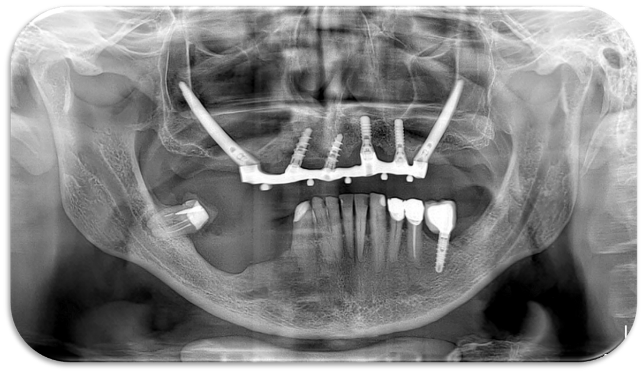

Nel secondo caso, invece, viene affrontata una situazione clinica complessa (Figura 4).

Il paziente, maschio, 63 anni, di etnia caucasica, è stato riabilitato dapprima con impianti tradizionali e impianti zigomatici; successivamente, viene programmato un intervento di implantologia guidata (Figura 5) per gestire la grave atrofia del settore 4 (Figure 6-7).